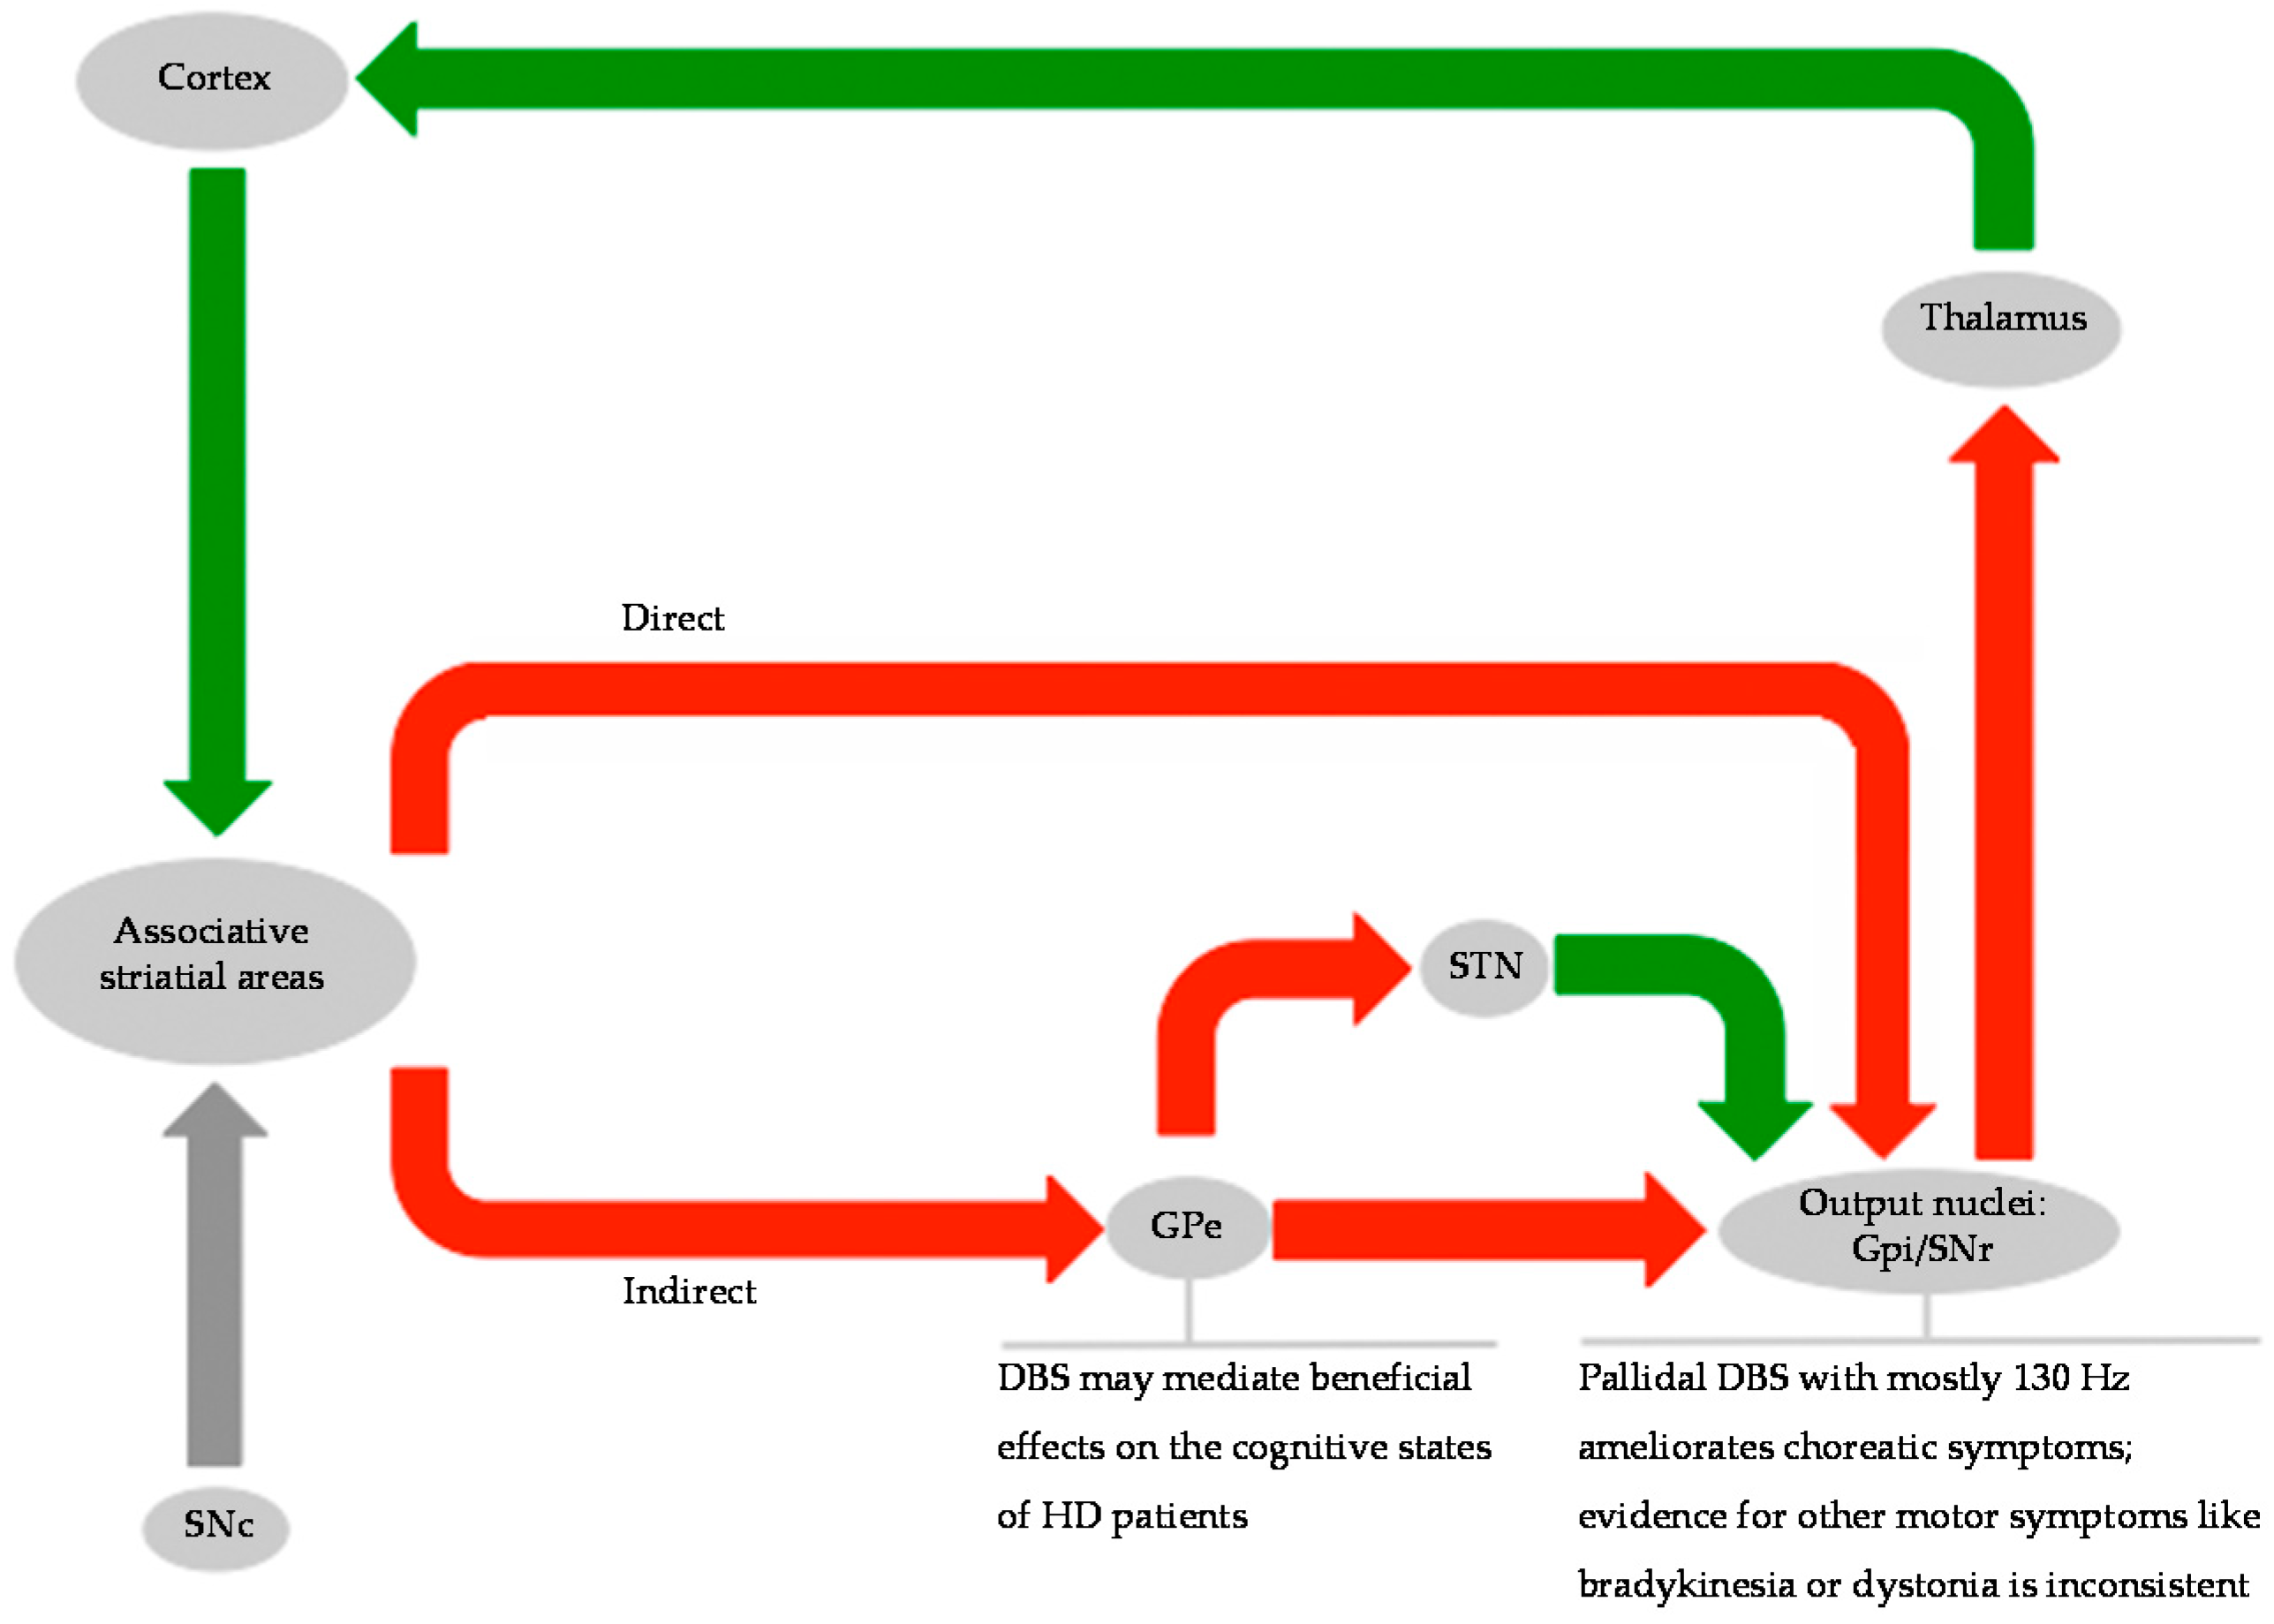

3. Invasive Assessment of the Basal Ganglia Network in HD

4. Clinical Implications of DBS in HD

4.1. Clinical Implications of DBS on Hyperkinetic and Hypokinetic Symptoms